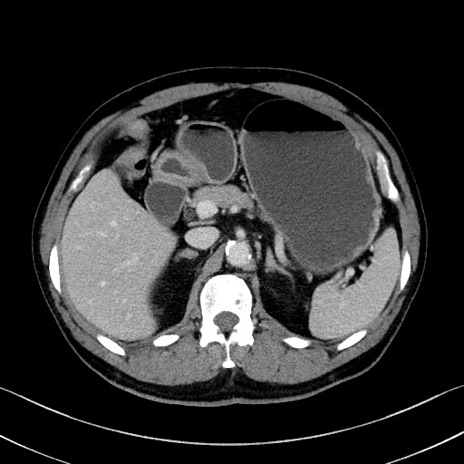

症例35(横断像)

【症例】70歳代 男性

【主訴】腹部膨満、嘔吐

【現病歴】昨日より腹部膨満感出現。本日増悪し、仙痛出現。嘔吐あり、受診。

【既往歴】糖尿病、胆摘後

【身体所見】BP 149/80mmHg、HR 74/min、BT 35.9℃、腹部:膨満、軟、圧痛なし。腸雑音減弱あり。上腹部正中切開瘢痕あり。

【データ】WBC 13500、CRP 1.72